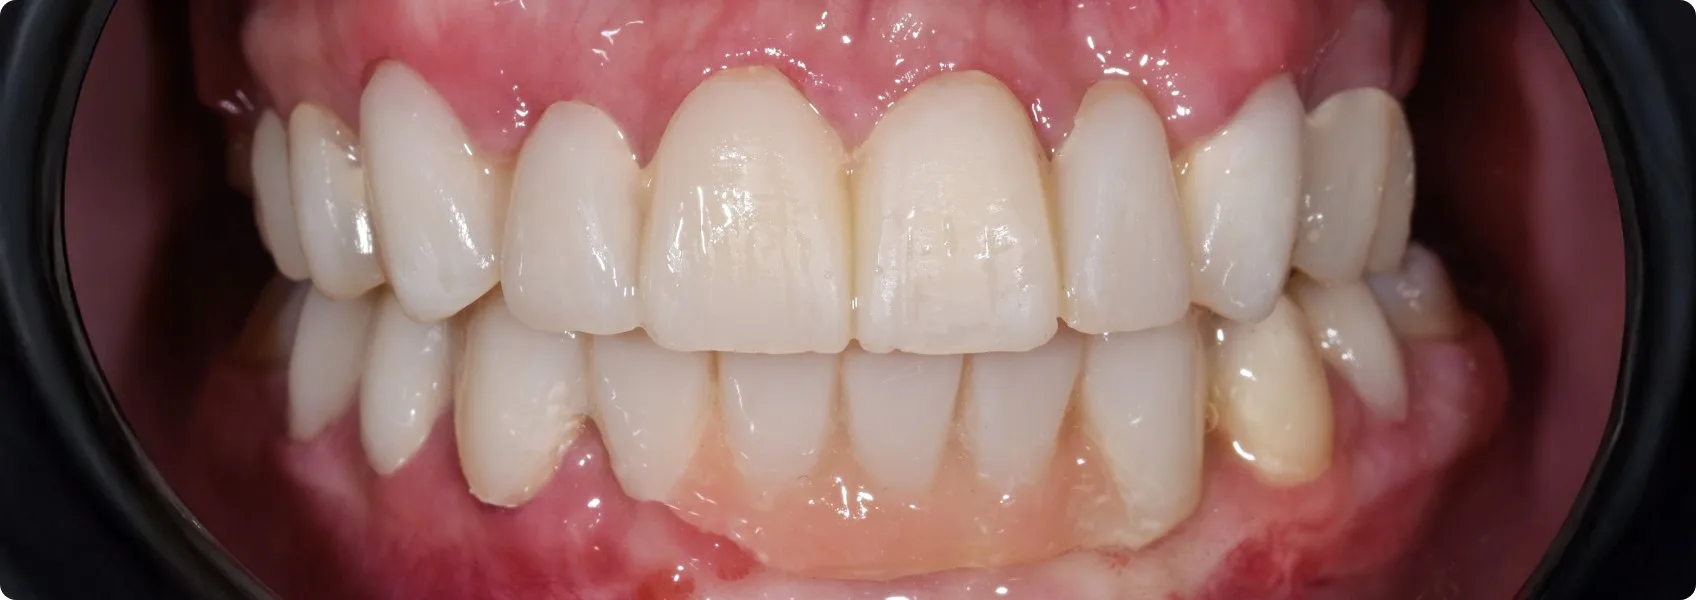

Po zabiegach chirurgicznych i oszlifowaniu Pacjent nie pozostaje bez zębów. Na czas gojenia i przygotowywania przez laboratorium pracy ostatecznej zakładamy prowizorium, czyli uzupełnienie tymczasowe.

To szalenie istotny krok! Po pierwsze, chroni przygotowane zęby i miejsca po zabiegach. Po drugie, od razu przywraca Pacjentowi możliwość całkiem normalnego funkcjonowania.

Po trzecie, w NDC prowizorium wykonujemy na podstawie wcześniejszego wax-upu, przez co jego kształt jest już bardzo zbliżony do finalnej pracy. Dzięki temu Pacjent ma tygodnie, a czasem i miesiące, by oswoić się w domu z nowym kształtem zębów, nowym zgryzem i ocenić wstępną estetykę.

Dla nas to również cenny etap diagnostyczny – możemy obserwować, jak Pacjent adaptuje się do zmian i bez dodatkowych kosztów wprowadzić poprawki, jeśli są potrzebne.